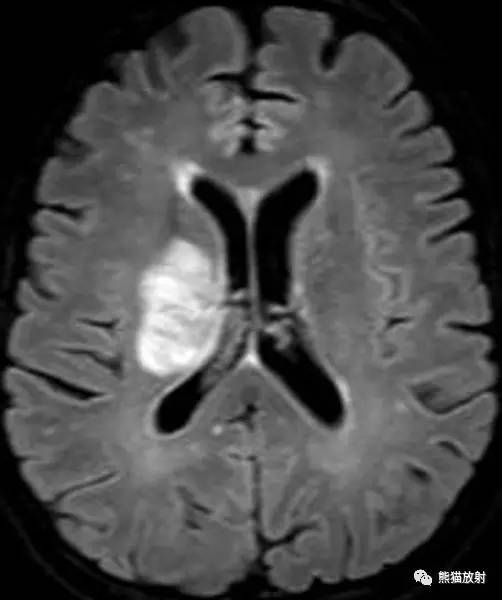

MRI表现:FLAIR示双侧额叶白质高信号灶,胼胝体前部及外周弥散受限,无明显占位效应,增强扫描无强化。

FLAIR、DWI和 ADC图示:右侧放射冠和基底节区可见 T2 高信号病变,不伴有脑水肿,边缘部分扩散受限。

增强示病灶外缘轻度强化; MRS示 Cho 和 NAA 峰降低,脂乳酸峰值保留;免疫组化结果提示阳性染色为 JC 病毒。